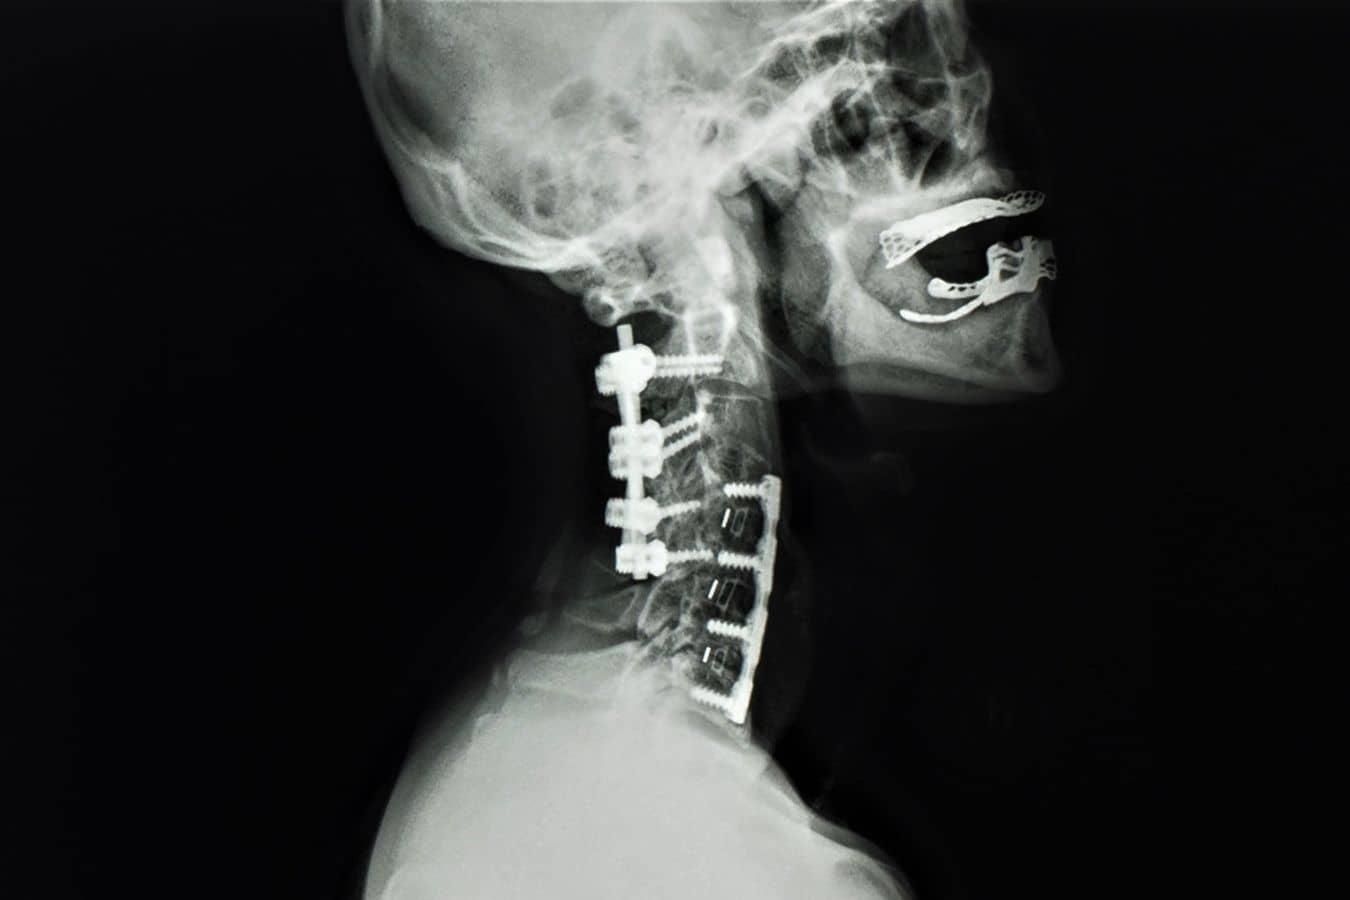

This is the approach when compression is primarily from the front, from disc herniations or bone spurs pushing backward into the spinal cord. We go through a small incision in the front of the neck, remove the disc and any bone spurs, decompress the cord and nerve roots, and fuse the segment with a cage or bone graft. Sometimes removing more of the bone, called corpectomy or partial corpectomy, is necessary to achieve decompression of the spinal cord.

Anterior-posterior fusion

For more severe cases, particularly multi-level compression with instability or significant kyphotic alignment, we sometimes need to decompress and stabilize from both the front and the back. This is a bigger surgery with a longer recovery, but in certain patients it’s the only way to adequately decompress the cord and maintain spinal alignment.

Posterior laminoplasty

When the compression spans multiple levels and the cervical spine has maintained its normal lordotic curve (forward curve), we can open up the spinal canal from the back by hinging open the lamina rather than removing it entirely. Laminoplasty preserves more motion than a posterior fusion and avoids the need to approach from the front. It’s a good option for patients with three or more levels of stenosis who have preserved alignment.